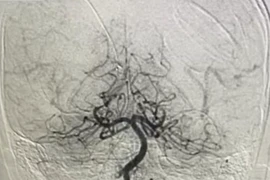

Bệnh nhân 31 tuổi mắc sởi biến chứng viêm phổi điều trị tại Viện Y học nhiệt đới Bạch Mai - Ảnh BVCC